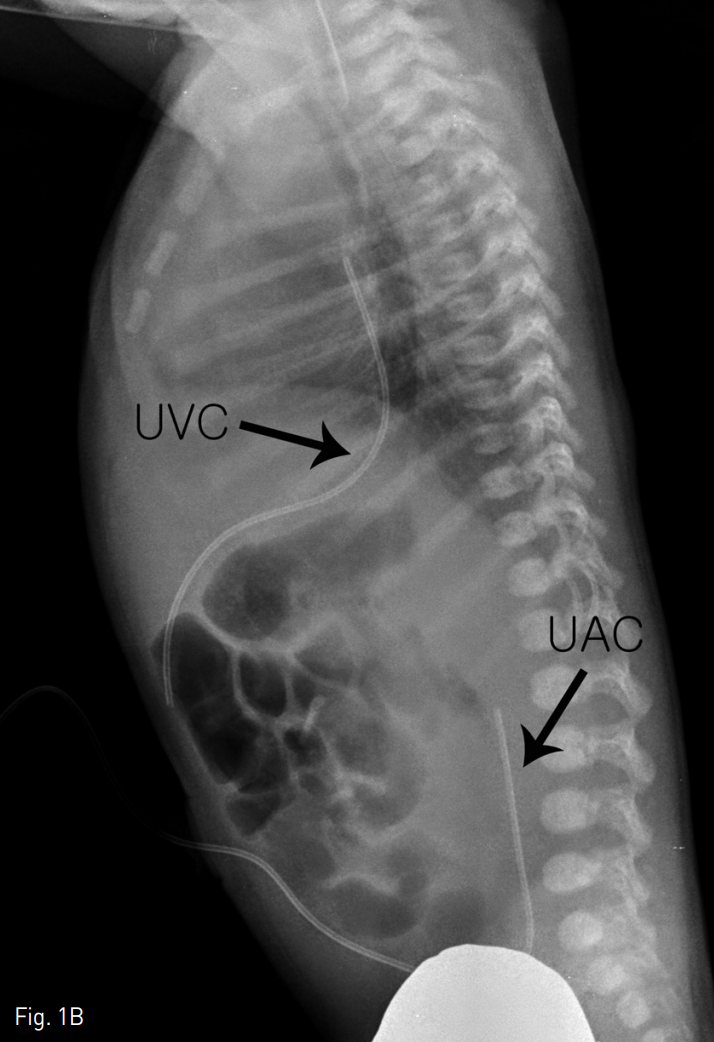

단순 X-ray촬영상 절단된 제대정맥관이 제대정맥과 우심방 사이에 관찰되었다(Fig. 1).

Fig. 1B

Anteroposterior (A) and lateral (B) plain x-rays showing the broken UVC between the umbilical vein and right atrium